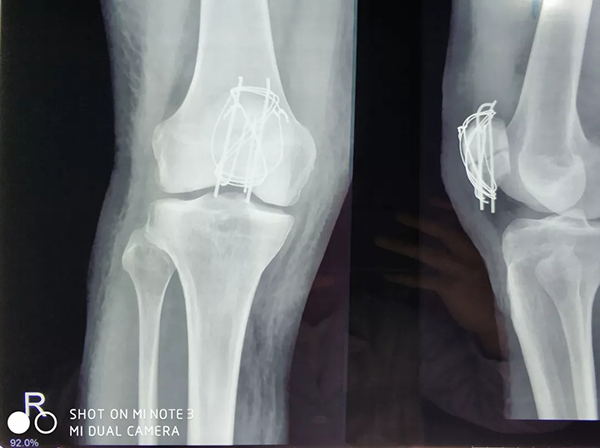

近日,廣安醫(yī)院關(guān)節(jié)科羅軍主任帶領(lǐng)科室團(tuán)隊(duì)成員為一名來(lái)自俄羅斯的患者成功施行了右髕骨粉碎性骨折切復(fù)內(nèi)固定手術(shù)治療,術(shù)后三天患者能自行起床活動(dòng)。

患者從遙遠(yuǎn)的俄羅斯來(lái)到美麗的舟山群島船廠指導(dǎo)工作,旅途中不慎跌倒,導(dǎo)致右髕骨粉碎性骨折,需行手術(shù)治療,患者來(lái)到廣安醫(yī)院就診,然而語(yǔ)言不通,患者只能聽(tīng)懂簡(jiǎn)單的英文,怎么辦?機(jī)智的易觀俊主治醫(yī)師用手機(jī)上的翻譯軟件,搭好了醫(yī)患溝通的橋梁。